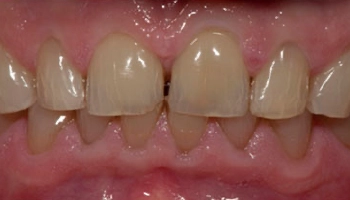

Trauma: Central Incisor veneers

Before and after images of central incisor veneers. Before and after images of central incisor veneers.